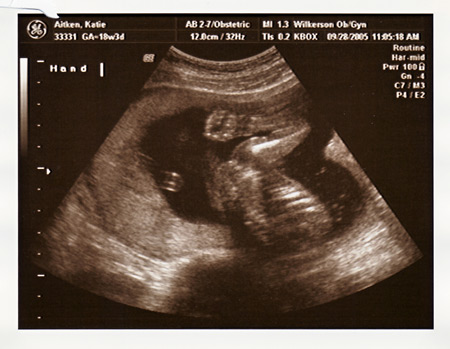

I had my ultrasound today, and found out everything is perfect and in place. We are so excited that Maeve will have a little sister to play with!!!